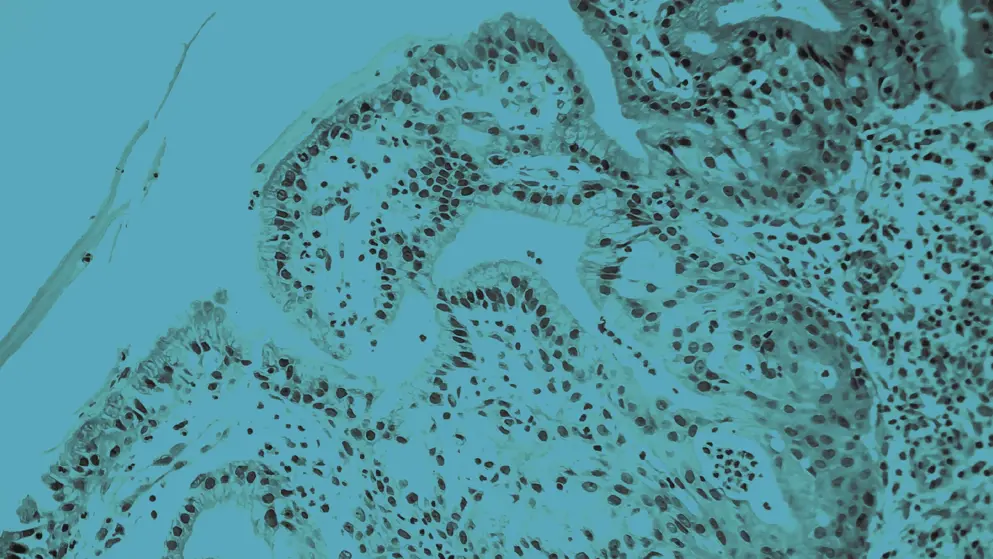

Nasal polyposis is a condition characterised by the presence of multiple nasal polyps on the lining of the nasal passages and sinuses. Nasal polyps are benign growths or swellings that can be caused by chronic inflammation, recurring infections, and drug sensitivity1. Symptoms of nasal polyposis include nasal obstruction, nasal discharge, facial pain, and a reduced sense of smell (anosmia) or taste. Nasal polyp complications include obstructive sleep apnoea, asthma flare ups, and sinus infections.

Nasal polyps are associated with inflammatory conditions including asthma and allergic rhinitis or chronic rhinosinusitis (CRS), often referred to as chronic rhinosinusitis with nasal polyps (CRSwNP)2. Asthma and CRSwNP often coexist, sharing pathophysiological mechanisms of inflammation that may underpin nasal polyp formation2,3. Other conditions associated with nasal polyposis include cystic fibrosis and Churg-Strauss syndrome4.